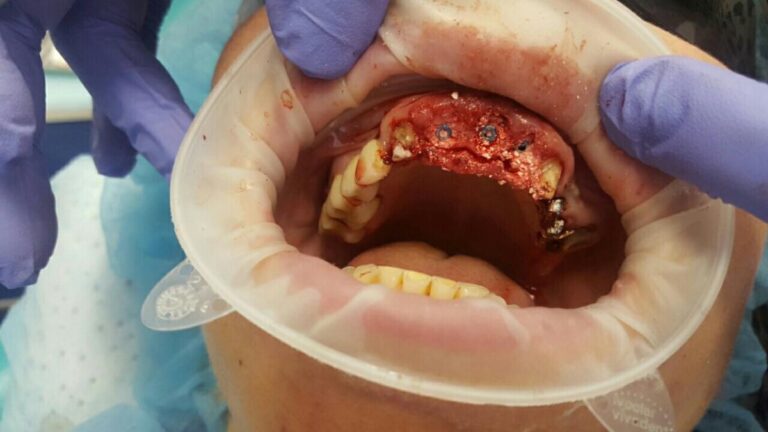

A patient case to the dental clinic with complaint connected with frond teeth defects. After the examination, he decided to provide dental treatment that includes immediate implantation of Alpha Dent implants. During the surgery he has placed 3 Alpha Dent implants in extracted teeth alveolar sockets. Then he placed allomaterial for bone regeneration over implants and sutured the wound.